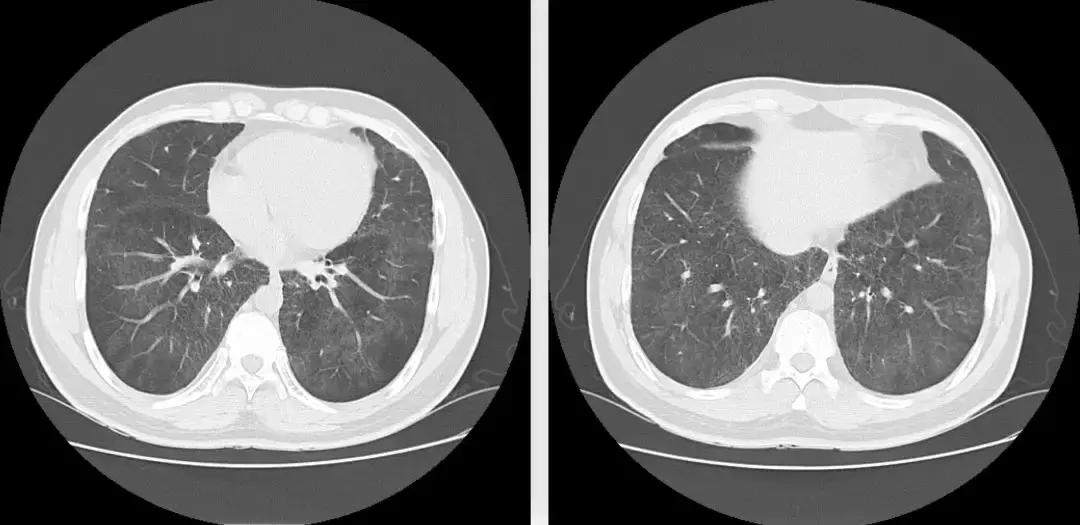

复查胸部CT(2018-1-29),对比原片如下图:

1、两肺野弥漫病变较前未见明显变化,两肺上叶陈旧病变同前

2、左肺下叶片状密度增高影较前范围增大,密度增高

3、纵膈内多发淋巴结,大者位于气管隆突下,短径约1.1cm,较前未见明显变化;余基本同前。